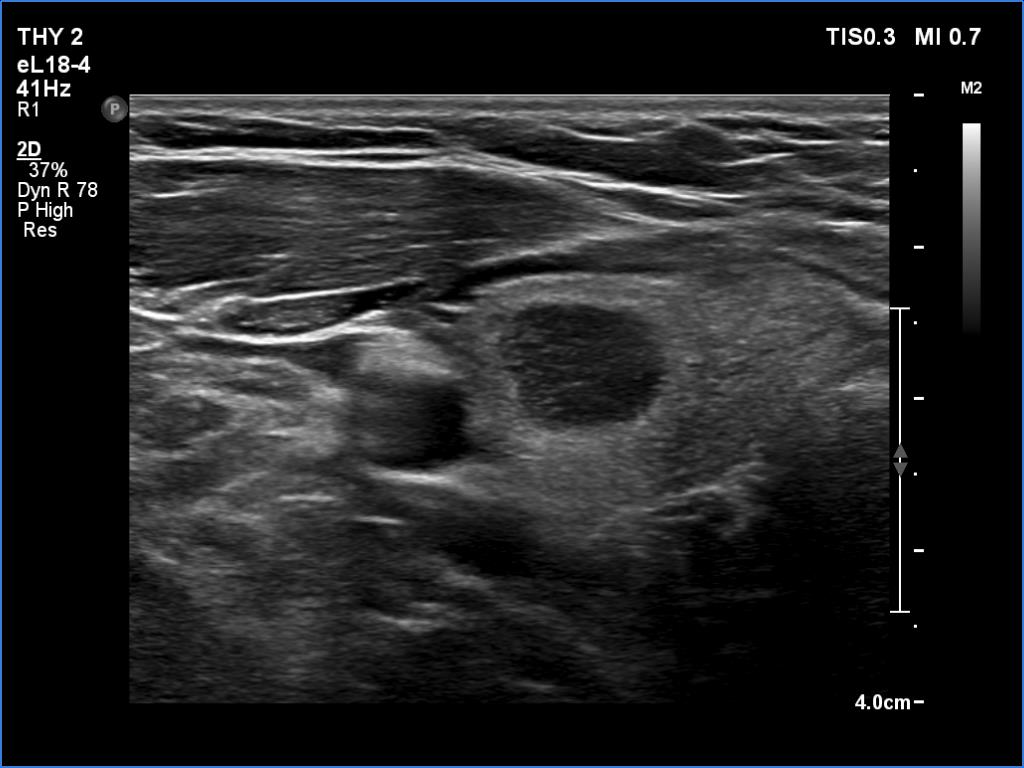

Ultrasonography. The thyroid was echonormal and presented several minimally-moderately hypoechoic areas. One of them, which was located in the central part of the right lobe was deeply hypoechoic and corresponded to pathological nodule. The other lesions seemed to be not true nodules but more active foci of thyroiditis.

Comment. It is worth comparing the deeply hypoechoic nodule with the other discrete lesions. The former has regular, sharp borders, and its echogenicity differs from other areas of the thyroid. These are the main clues of differentiation of a true nodule from a discrete lesion of Hashimoto's thyroiditis.